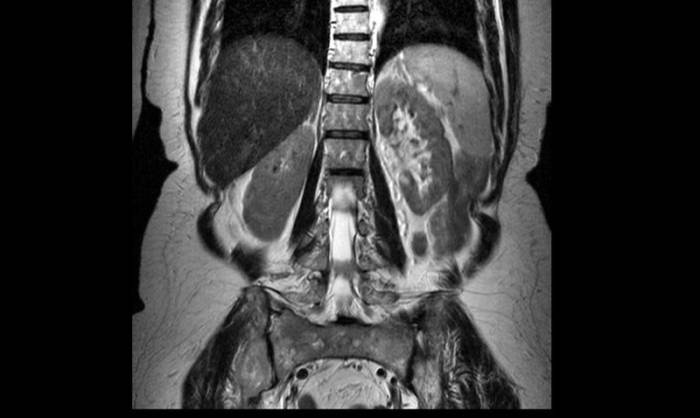

На МР-изображении стрелками показан ушиб шестого грудного позвонка (визуализируется отек костных структур без деформации тела позвонка)